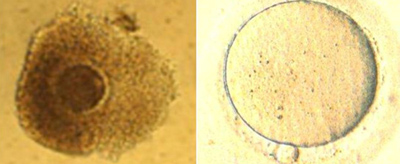

ĶŠģÕŖ®ÕŁĄÕī¢’╝łAssistedHatching’╝ē

Ķ¢äĶŹĘµ£ēµŖŚµŚ®ÕŁĢÕÆīµŖŚÕÅŚń▓ŠÕŹĄńØĆÕ║ŖńÜäõĮ£ńö©